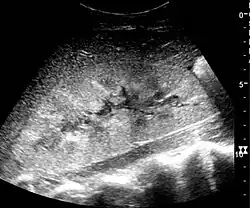

Complex cysts can have membranes dividing the fluid-filled center with internal echoes, calcifications or irregular thickened walls. The complex cyst can be further evaluated with Doppler US, and for Bosniak classification and follow-up of complex cysts, either contrast-enhanced ultrasound (CEUS) or contrast CT is used (Figure 6). The Bosniak classification is divided into four groups going from I, corresponding to a simple cyst, to IV, corresponding to a cyst with solid parts and an 85–100% risk of malignancy.[1] In polycystic kidney disease, multiple cysts of varying size in close contact with each other are seen filling virtually the entire renal region. In advanced stages of this disease, the kidneys are enlarged with a lack of corticomedullary differentiation (Figure 7).[1]

Figure 7. Advanced polycystic kidney disease with multiple cysts.[1]